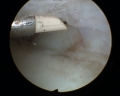

Les progrès techniques de la chirurgie mini-invasive du poignet ont permis de réaliser l'ablation de ces kystes sous arthroscopie, c'est-à-dire au moyen de deux mini incisions permettant, l'une d'introduire une caméra de 1,9 à 2,7 mm de diamètre et l'autre des instruments mécaniques et de radiofréquence de 2-3 mm de diamètre (figure 2). La base d'implantation du kyste est repérée (une IRM ou une échographie préalable ont guidé le choix des petits incisions-figure 3) et retirée. Le liquide mucoïde s'écoule alors dans l'articulation et est aspiré alors que la paroi du kyste est excisée par la profondeur sans nécessité d'incision supplémentaire (figure 4). On visualise ainsi les tendons extenseurs des doigts et du poignet qui doivent être contrôlés et protégés durant toute l'intervention (figure 5), constituant le seul risque spécifique de cette arthroscopie. l'intérêt de cette technique n'est pas qu'esthétique, bien que l'indication du geste opératoire soit essentiellement cosmétique (figure 6) mais surtout plus logique et efficace que la chirurgie dite classique, car il permet le repérage et l'excision du point de départ de cette "tumeur" bénigne, diminuant ainsi le risque théorique de récidive. On peut ainsi diagnostiquer et retirer des petits kystes du ligament scapho-lunaire (figure 7), il y a encore peu surnommés "occult ganglions" car peu accessibles aux autres procédés d'exploration du poignet, ils peuvent être douloureux notamment lors des appuis en flexion dorsale.